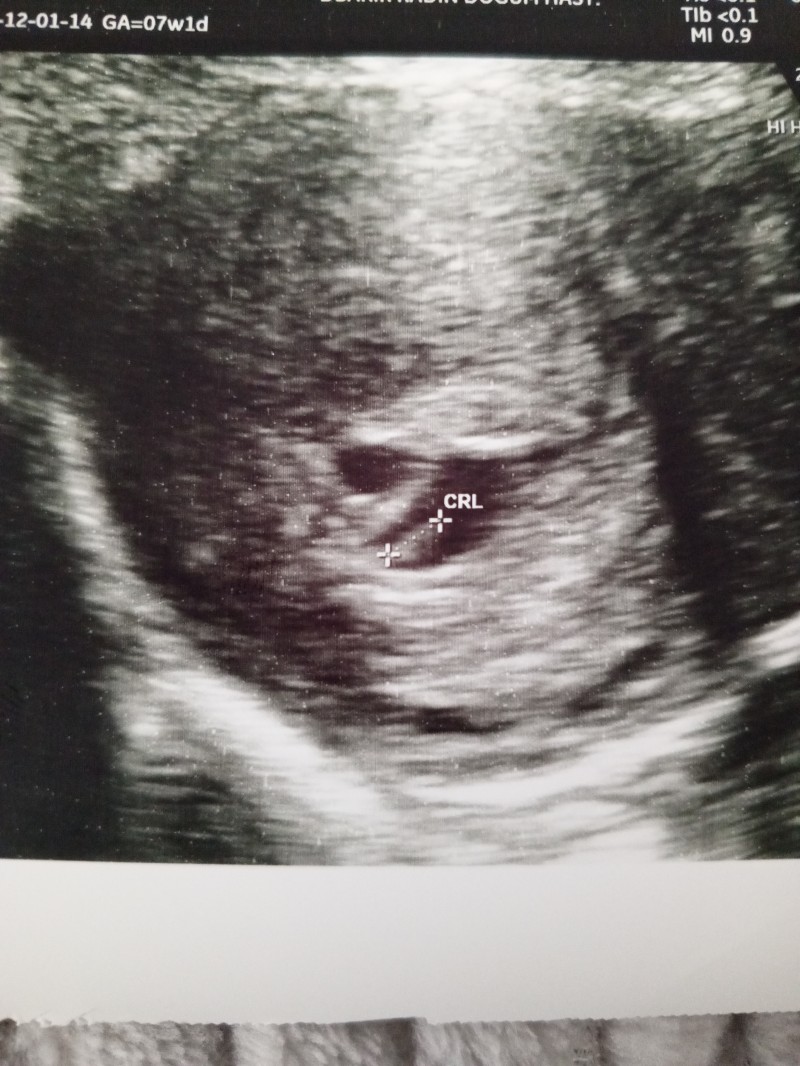

kızlar bugün 6+1 günlük oldum doktora gittim kalp atışını duyduk çok şükür ama şöyle ki doktor bir kese daha var dedi  10 gün sonra tekrar gel dedi bu ikiz demek mi ikiz olduğunu bu şekilde öğrenen var mı

bi kese daha varsa ikizdir canım

Ultrason kağıdında da görünüyor aslında ama içi henüz boş

Yapay zekaya attım orası için kanama alanı diyor

Yok ya kanama alanı olsa doktor anında söyler

Doktor daha çok kücük ama kese gibi görünüyor 10 gün sonra tekrar gel dedi ama kanama alanı falan demedi sadece kanaman var mı dedi yok dedim bide tedavi mi gördün yoksa doğal mı dedi doğal dedim başka bir şey demedi

Kanama alanı görseler derlerdi. İçime sinmez 10 gün beklemem dersen bir doktora daha git. BHCG değerin kaçtı